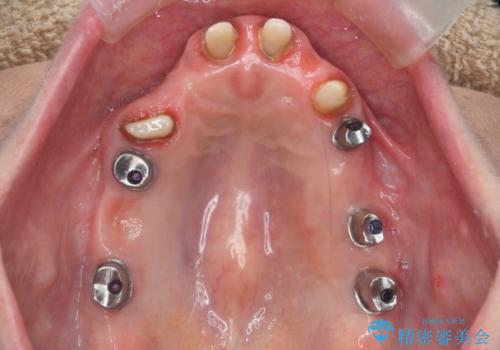

多発した虫歯による咬合崩壊 インプラントを用いた全顎治療

歯の破折・再発した大きな虫歯・根尖病変・歯の欠損、これらの問題を根管治療・歯周外科・インプラント治療・セラミック補綴を行うことで一つづつ解決し安定した咬合状となるよう治療を進めます。

口腔内全体を治療する全顎治療は、期間も長く外科を行う回数も多いためしっかりと通っていただくことが必要不可欠になります。